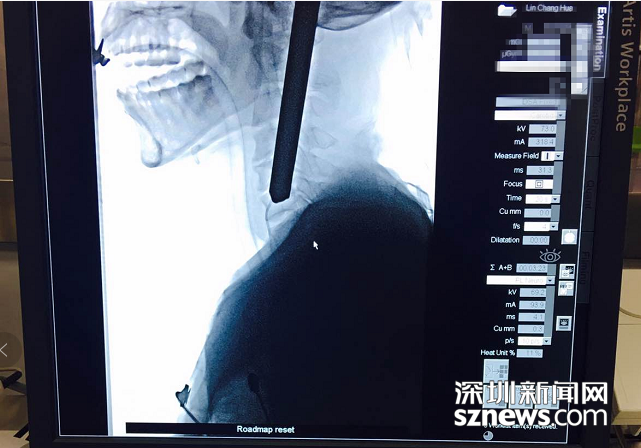

拍片顯示鋼筋深入患者頸部

北大深圳醫(yī)院接診后立即組織多學(xué)科會(huì)診,同時(shí)開(kāi)通顱腦外傷綠色通道。消防員先行將傷者的顱外鋼筋切除,隨后,神經(jīng)外科緊急行腦血管造影?紤]到鋼筋對(duì)大腦及腦血管可能造成的損傷,神經(jīng)外科團(tuán)隊(duì)決定立即為患者施行手術(shù)。